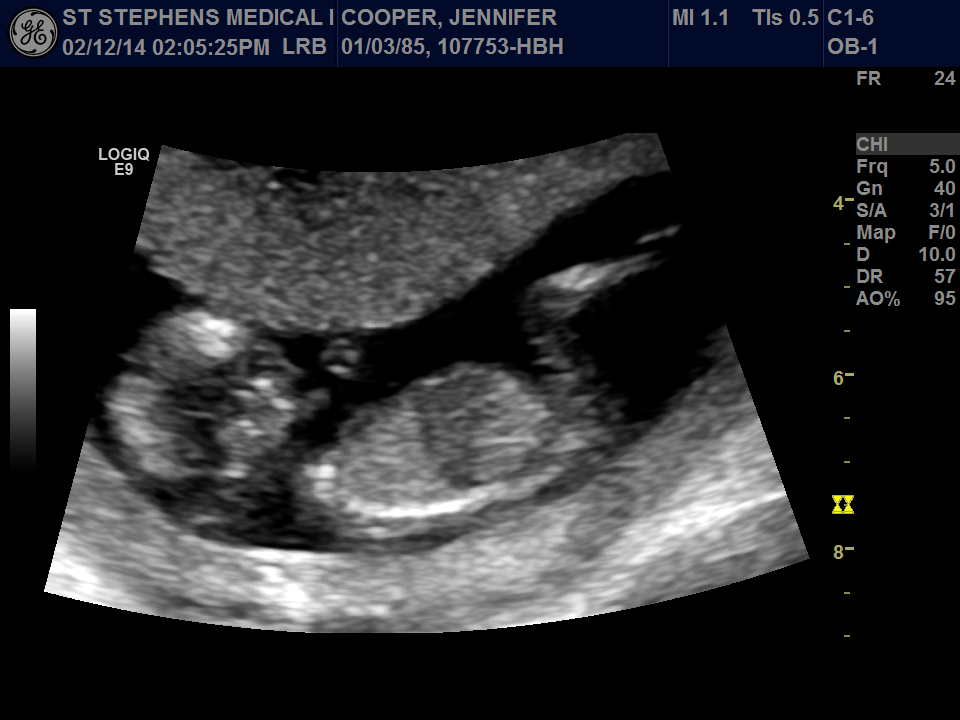

Attachment 22396Had my nuchal translucency ultrasound done yesterday at 12 weeks 4 days, images aren't too clear but wondering if anyone has any thoughts as to baby's gender?

Have added another picture which is a still from the video, unsure for certain whether it's the nub pictured or not.

Any insight at all would be appreciated.